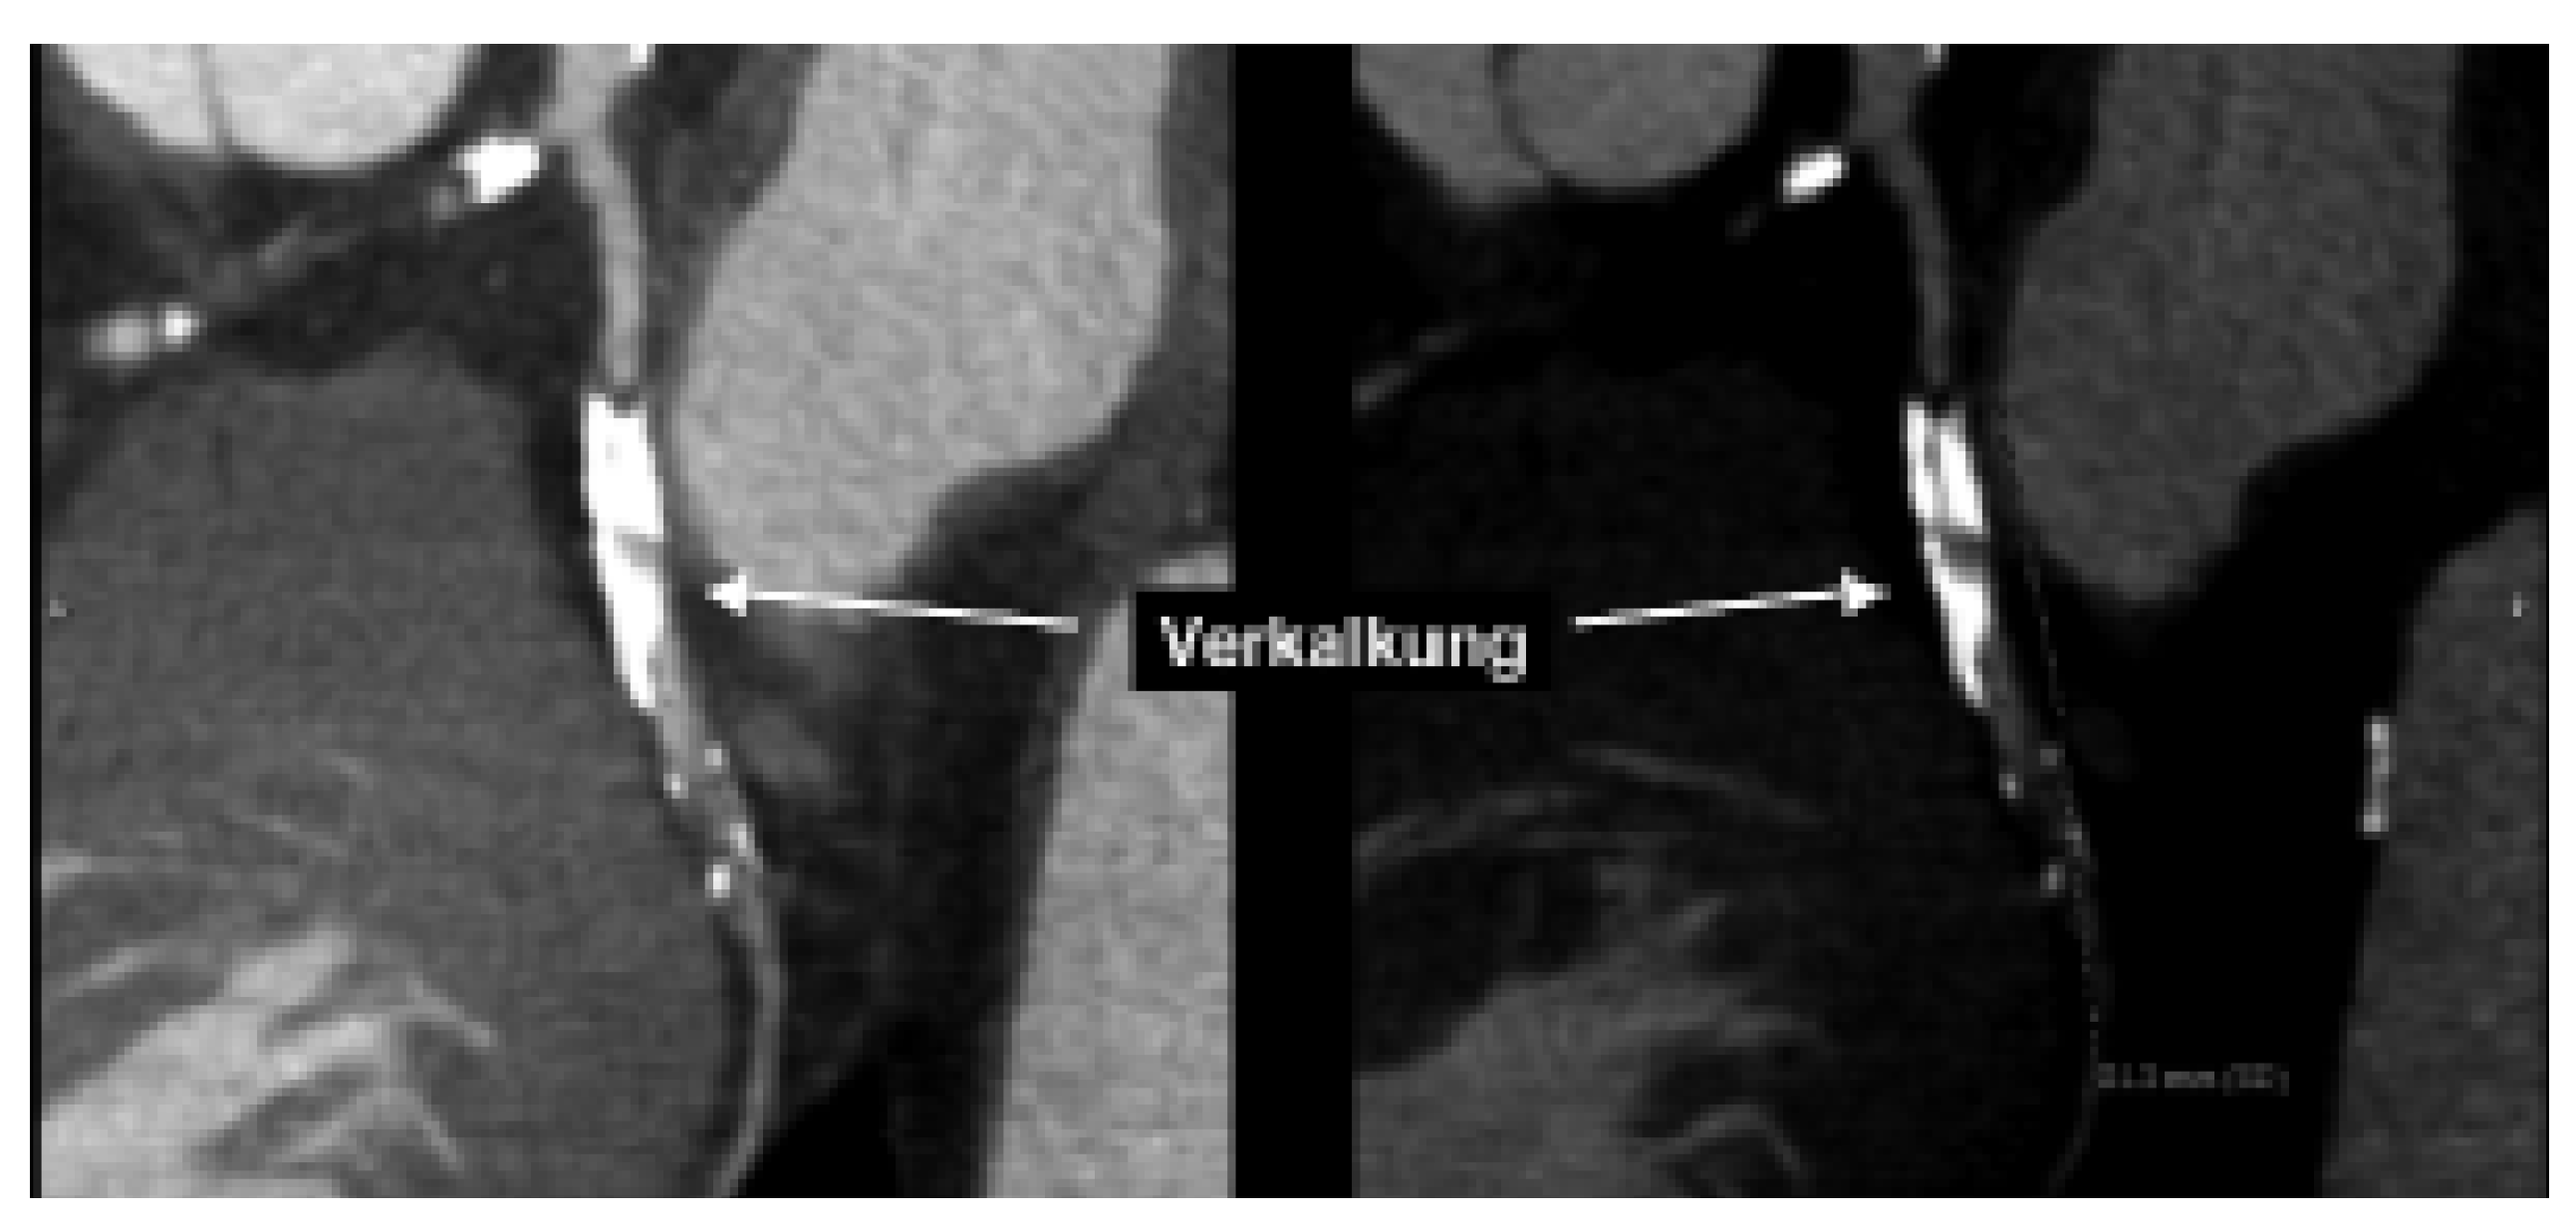

Abbildung 2. Darstellung einer schweren Verkalkung im Ramus circumflexus. Die ausgeprägte Verkalkung verunmöglicht eine korrekte Beurteilung bezüglich Lumeneinengung (links). Mit geeigneten Massnahmen bei der Bildverarbeitung kann dieses Problem teilweise etwas kompensiert werden.

Verkalkungen der Herzkranzgefässe beeinträchtigen allerdings auch erheblich die Darstellung des Lumens in der computertomographischen Angiographie (Abb. 2). Somit lässt sich in stark verkalkten Gefässen meist nicht sagen, ob es sich nur um ein krankes, d.h. arteriosklerotisch verändertes Koronarsegment handelt, oder ob es auch hämodynamisch relevant eingeengt ist. Vor allem bei älteren PatientInnen und solchen mit Diabetes und/oder Niereninsuffizienz, welche ausgeprägte Verkalkungen aufweisen, ist daher keine schlüssige Beurteilung des Lumens möglich. Zudem kann die EKG-getriggerte Untersuchung bei hoher Herzfrequenz, bei Vorhofflimmern und anderen Rhythmusstörungen, die bei etwa 5% der Patienten zu finden sind, nicht durchgeführt werden. Schliesslich sollte bei Patienten mit schwerer Herzinsuffizienz die Volumenbelastung durch das Kontrastmittel in Betracht gezogen werden. Auch durch Stents verursachte Artefakte stellen ein diagnostisches Problem dar (Abb. 3). Obschon die neuesten CT-Geräte sehr genau die Stent-Länge und den Durchmesser erfassen können, ist eine sichere Beurteilung des Lumens in vielen Fällen noch nicht möglich. Da bei der koronaren Herzkrankheit die Frage nach einer Intervention im Vordergrund steht, sei es eine kathetertechnische Stent-Implantation oder eine Bypass-Operation, ist die Erfassung von Koronarstenosen das Hauptziel dieser Untersuchungen. Entsprechend ist diese Einschränkung der Aussagekraft der computertomograpischen Koronarangiographie durch Gefässwandverkalkungen ein grosser Nachteil dieser Methode. Zusammenfassend ist daher der negativ prädiktive Wert der computertomographischen Koronarangiographie sehr hoch, d.h. bei fehlendem Nachweis von Kalzium und Einengungen lässt sich mit an Sicherheit grenzender Wahrscheinlichkeit eine koronare Herzkrankheit ausschliessen. Der positive prädiktive Wert behandlungsbedürftiger Koronarstenosen ist aber vor allem in der älteren Population, in welcher die koronare Herzkrankheit besonders häufig ist, immer noch stark eingeschränkt (Abb. 4). Unseres Erachtens können momentan wichtige klinische Entscheidungen (wie z.B., ob ein Patient aufgrund des Koronarbefundes mittels ACBPOperation oder PCI behandeln werden muss) nicht ausschliesslich anhand des CT-Befundes gefällt werden. Das Vorhandensein von Gefässverkalkungen hat den Einsatz dieser vielversprechenden Technik auch in anderen Gefässabschnitten (wie in den Karotiden [8,9]) beschränkt.